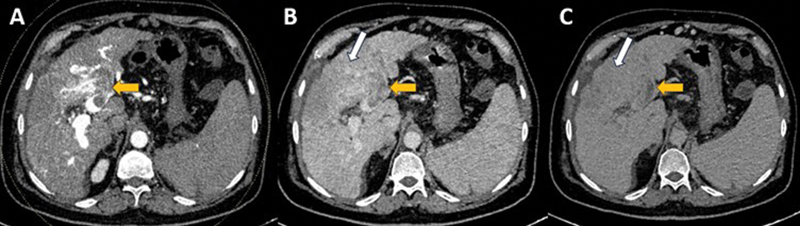

目的比较浸润性肝细胞癌(HCC)与结节性肝细胞癌(结节性肝癌)的多期增强ct (CECT)特征,评价浸润性肝细胞癌不同期CECT的显著性。材料和方法本回顾性研究纳入了2020年1月至2021年12月期间诊断为浸润性和结节性HCC的连续未接受治疗的肝硬化患者,基于多期CECT(包括动脉期、门静脉期和延迟期)。HCC的诊断依据肝成像报告和数据系统(LI-RADS) v2018标准(LR-4和LR-5病变)。浸润性hcc的特征是大的、不规则的、浸润性病变,分布在多个肝节段或肝叶。结节性hcc包括定义明确的肿瘤结节。两名放射科医生独立审查了所有CT图像。此外,还评估了动脉、门静脉和延迟期病变的显著性。结果158例患者中,结节性hcc 117例,浸润性hcc 41例;平均年龄:55.6±17.2岁;包括90例(56.9%)男性。动脉期高强化、门静脉/延迟期冲洗、延迟期增强胶囊与结节性hcc有显著相关性(p = 0.002、0.0001、p)。结论浸润性hcc与结节性hcc相比,主要LI-RADS表现较少,静脉血栓形成是诊断的重要线索。多相CECT的延迟期是识别这些病变的关键。

Objective  The aims of this study are to compare the multiphasic contrast-enhanced computed tomography (CECT) characteristics of infiltrative hepatocellular carcinoma (HCC) with nodular HCC and to assess the conspicuity of infiltrative HCC on different phases of CECT. Materials and Methods  This retrospective study comprised consecutive treatment-naive cirrhotic patients diagnosed with infiltrative and nodular HCC between January 2020 and December 2021 based on a multiphasic CECT (comprising arterial, portal venous, and delayed phases). The diagnosis of HCC was based on the Liver Imaging Reporting and Data System (LI-RADS) v2018 criteria (LR-4 and LR-5 lesions). Infiltrative HCCs are characterized by large, irregular, permeative lesions spread over multiple liver segments or lobes. Nodular HCCs comprise well-defined tumor nodules. Two radiologists independently reviewed all CT images. Additionally, lesion conspicuity on the arterial, portal venous, and delayed phases was assessed. Results  One hundred fifty-eight patients (117 nodular and 41 infiltrative HCCs; mean age: 55.6 ± 17.2 years; 90 [56.9%] males) were included. Arterial phase hyperenhancement, portal venous/delayed phase washout, and delayed phase enhancing capsule were significantly associated with nodular HCCs ( p  = 0.002, 0.0001, and <0.0001, respectively). Portal vein, hepatic vein thrombosis, biliary dilatation, and ascites were significantly associated with infiltrative HCCs ( p  < 0.0001, 0.004, <0.0001, and 0.003, respectively). The interobserver agreement for the conspicuity of infiltrative HCC was the highest for the delayed phase (weighted kappa = 0.611). Conclusion  Infiltrative HCCs show the major LI-RADS features less frequently compared with nodular HCCs, and venous thrombosis is an important clue to the diagnosis. The delayed phase of multiphasic CECT is critical to identifying these lesions.